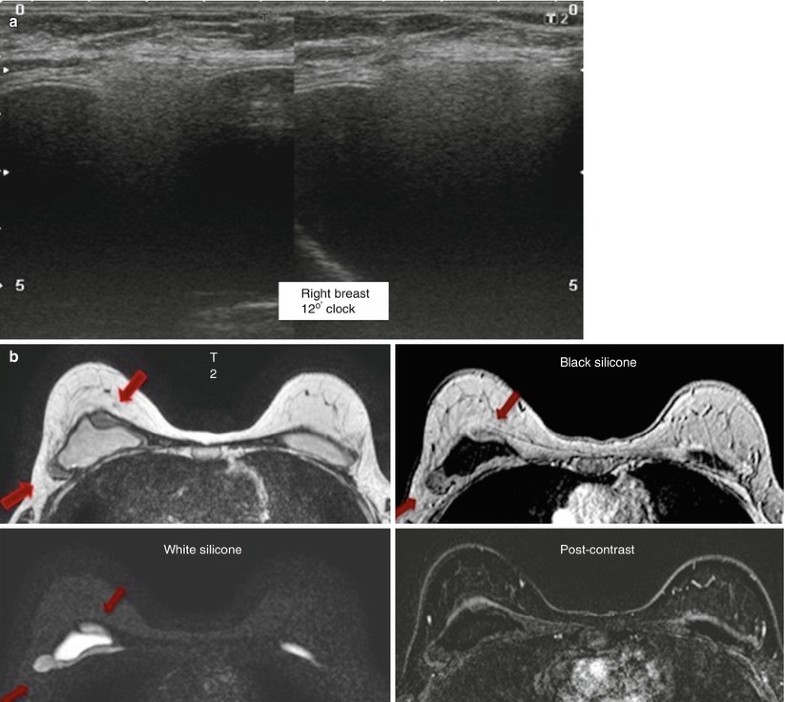

Snowstorm Lymph Node. Snowstorm sign on breast ultrasound imaging represents the presence of free silicone droplets mixed with breast tissue giving a characteristic heterogeneous echogenic appearance with dispersion of the ultrasound beam. It is characterized by the presence of many hydropic villi which gives the ultrasonographic appearance of a central heterogeneous mass having a solid, hyperechoic area and interspersed with a multitude of cystic areas and filling the entire. Snowstorm sign in obstetric imaging is classically seen in complete hydatiform mole. It is considered the most reliable sign of extracapsular breast implant rupture 1.a similar appearance may be seen in axillary nodes in.

Snowstorm sign on breast ultrasound imaging represents the presence of free silicone droplets mixed with breast tissue giving a characteristic heterogeneous echogenic appearance with dispersion of the ultrasound beam. It is characterized by the presence of many hydropic villi which gives the ultrasonographic appearance of a central heterogeneous mass having a solid, hyperechoic area and interspersed with a multitude of cystic areas and filling the entire. Snowstorm sign in obstetric imaging is classically seen in complete hydatiform mole. The sensitivity and specificity in diagnosing silicone lymphadenopathy were calculated for the snowstorm sign on us and the mri silicone signal. It is considered the most reliable sign of extracapsular breast implant rupture 1.a similar appearance may be seen in axillary nodes in. All nodes were evaluated by us, and 18 of 41.